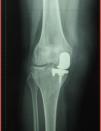

Mujer de 72años, con antecedentes de artroplastia unicameral de rodilla derecha desde hacía 12años, que acude a nuestra consulta por dolor en dicha rodilla de 6meses de evolución, sin fiebre ni síntomas sistémicos. En la exploración física se objetivó tumefacción de dicha rodilla. La radiografía mostró prótesis parcial en el compartimento medial, sin alteraciones (fig. 1). Se realizó artrocentesis, obteniendo un fluido oscuro (fig. 2), con 150 células (75% polimorfonucleares), glucosa 90mg/dl, proteínas 2mg/dl. El cultivo del líquido articular fue negativo. Con la sospecha de metalosis, la paciente fue derivada a la consulta de traumatología, y la prótesis fue sustituida por una prótesis total. Una muestra de tejido sinovial fue enviada a anatomía patológica, mostrando macrófagos con pigmento negruzco en su citoplasma y linfocitos (figs. 3 y 4). Actualmente la paciente se encuentra asintomática.

La metalosis se define como una corrosión debida a la erosión de los componentes metálicos, que producen partículas que inducen una reacción de hipersensibilidad. Generalmente es asintomática y la aparición de dolor o rigidez se debe al aflojamiento secundario de la prótesis1. Su sospecha puede surgir al apreciar zonas osteolíticas lobuladas con o sin aumento de los tejidos blandos adyacentes en la radiografía simple, debiendo realizarse diagnóstico diferencial con movilización aséptica de la prótesis y con artritis séptica2. Macroscópicamente aparece una pigmentación negruzca de la articulación junto con un líquido sinovial oscuro. Microscópicamente podemos apreciar partículas metálicas, ya sean libres o absorbidas por macrófagos, con un infiltrado linfocitario que sugiere una respuesta inmune3. El tratamiento consiste en el reemplazo de la prótesis y la realización de una sinovectomía con el fin de eliminar las partículas metálicas3.